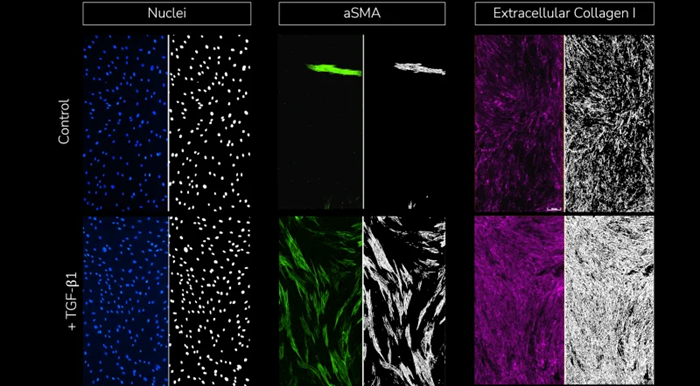

Split view images with fluorescent staining of cell nuclei, α-SMA, and extracellular collagen I (left) and respective segmentation analysis masks (right) for each stained marker under control (un-stimulated, top) and TGF-β1 stimulated conditions (bottom). Image Credit: Newcells Biotech